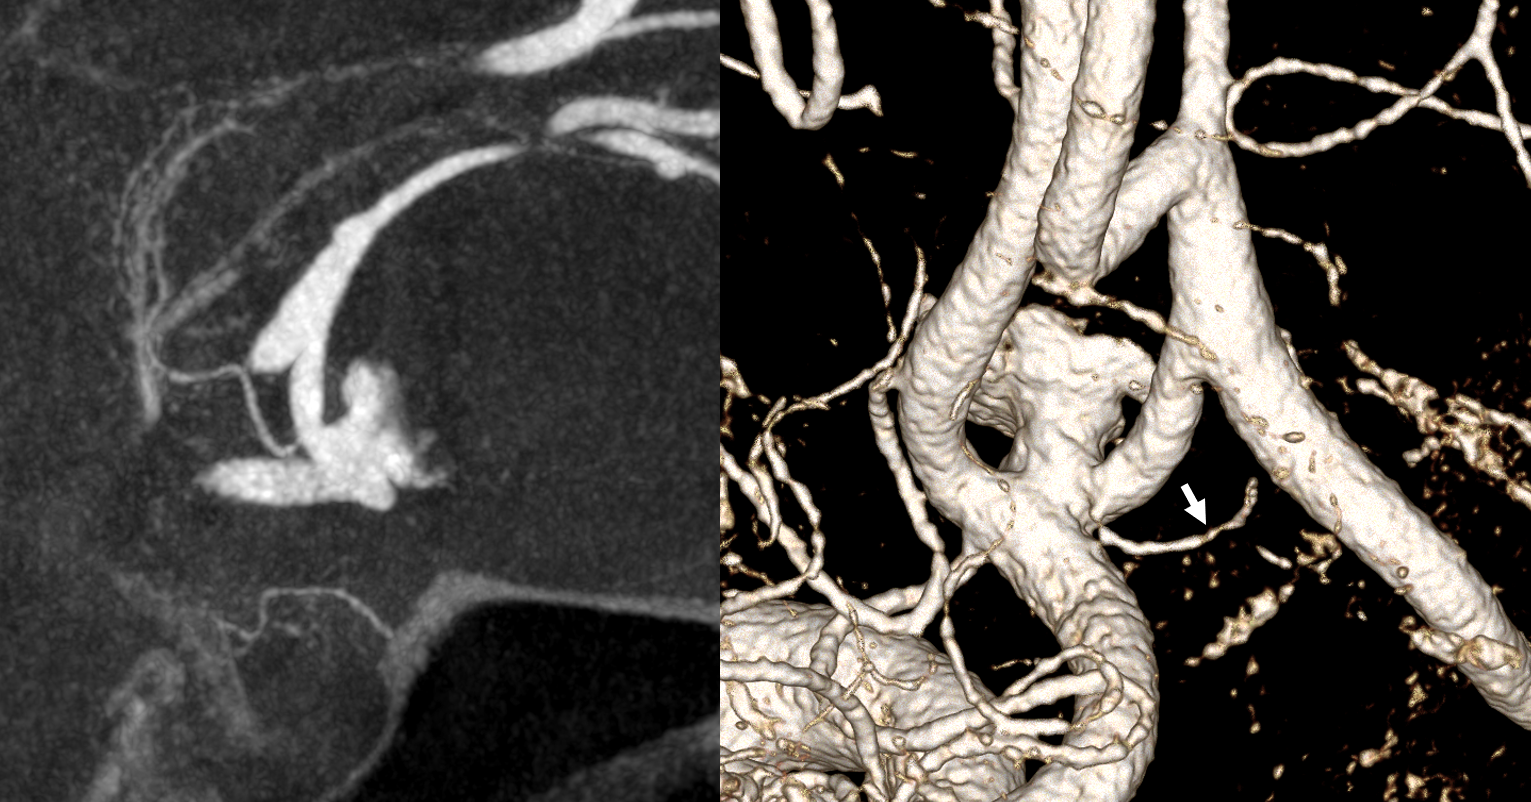

Spins are good

A secondary reconstruction and detailed analysis is better. What does arrow point to?

Spin

A better unsubtracted spin